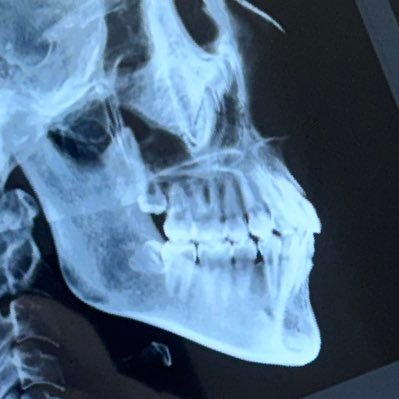

両顎+プレ除去+再固定 済 Joined March 2020-

107 Followers 232 Following 顎変形症治療中で情報収集しています。下顎前突、非対称。22.08〜治療開始/22.09〜ブラケット装着/上4番、親知らず抜歯/24.07両顎手術済/25.05ブラオフ/25.06プレート除去+鼻中隔湾曲手術済(new)無言フォロー申し訳ございません🙇♀️🙇♀️🙇♀️

221 Followers 217 Following 出っ歯すきっ歯を治したくて2020.1より部分矯正8ヶ月実施、終了間際で噛み合わせおかしくなり顎の痛みが出て、顎変形症(骨格性上顎前突症、下顎後退症)診断。2022.1.18より術前矯正開始→2023.4.20手術済。プレート除去2024.5.17です。左耳聞こえず片耳難聴です。無言フォロー申し訳ありません。

243 Followers 163 Following 顎変形症(上顎前突 下顎後退 左右非対称) 2023/11/28にルフォーI型+ssro済 2024/7/9オトガイ+プレ除去+上顎再固定2024/9/13済